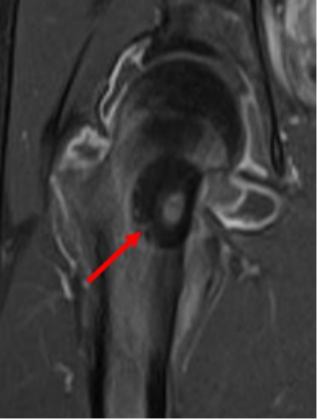

症例

腎がんが多発するフォンヒッペルリンドウ病の患者様で、左腎はすでに他院で摘出されており、右腎しかない単腎の症例。ラジオ波治療後に腫瘍は完全に死滅している。この患者様はこの後、もう一つ別にあった腎がんも同様に治療された。このようにラジオ波治療は腎機能を低下させず、繰り返して治療できることから、このような単腎の多発腎がんでも治療が可能である。